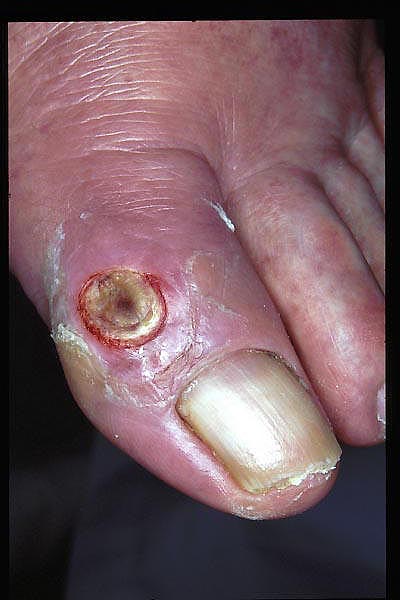

Paroniquia por recorte de uña.